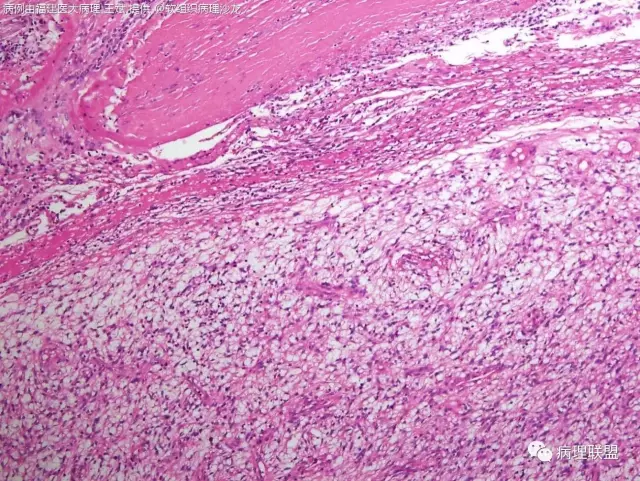

38岁,女性,手部小指背侧皮下肿物,3×2cm(病例由福建医大病理 王斌提供,致谢!)

是的,可以部分有粘液变,我见过的

血管瘤样纤维组织细胞瘤的肿瘤周围有淋巴细胞鞘,结节状分布,有假包膜,出血囊性变的为其主要特点,当然少数病例可以没有出血囊性变却出现粘液变。肿瘤细胞有一定异形性,属于低度恶性或交界性,最好做个FISH,看看有没有EWSR1-CREB1融合基因,刚查了一下,血管瘤样纤维组织细胞瘤还有另一种EWSR1-ATF1融合基因,无论是哪种,用EWSR1分离探针就可以检测